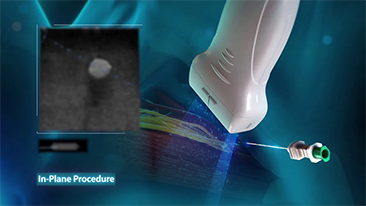

Hemanjiyom veya karaci?er kanseri gibi fokal karaci?er lezyonlar? i?in, ultrason kontrast g?rĂŒntĂŒlemesi ?nemli bir rol oynar. Ultra geni? lineer olmayan UWN+ kontrast g?rĂŒntĂŒleme teknolojisi, daha dĂŒ?ĂŒk MI ve daha uzun perfĂŒzyon sĂŒresi g?zlemi ile daha iyi penetrasyon, daha yĂŒksek kontrast doku oran? elde edilmesine yard?mc? olabilir.